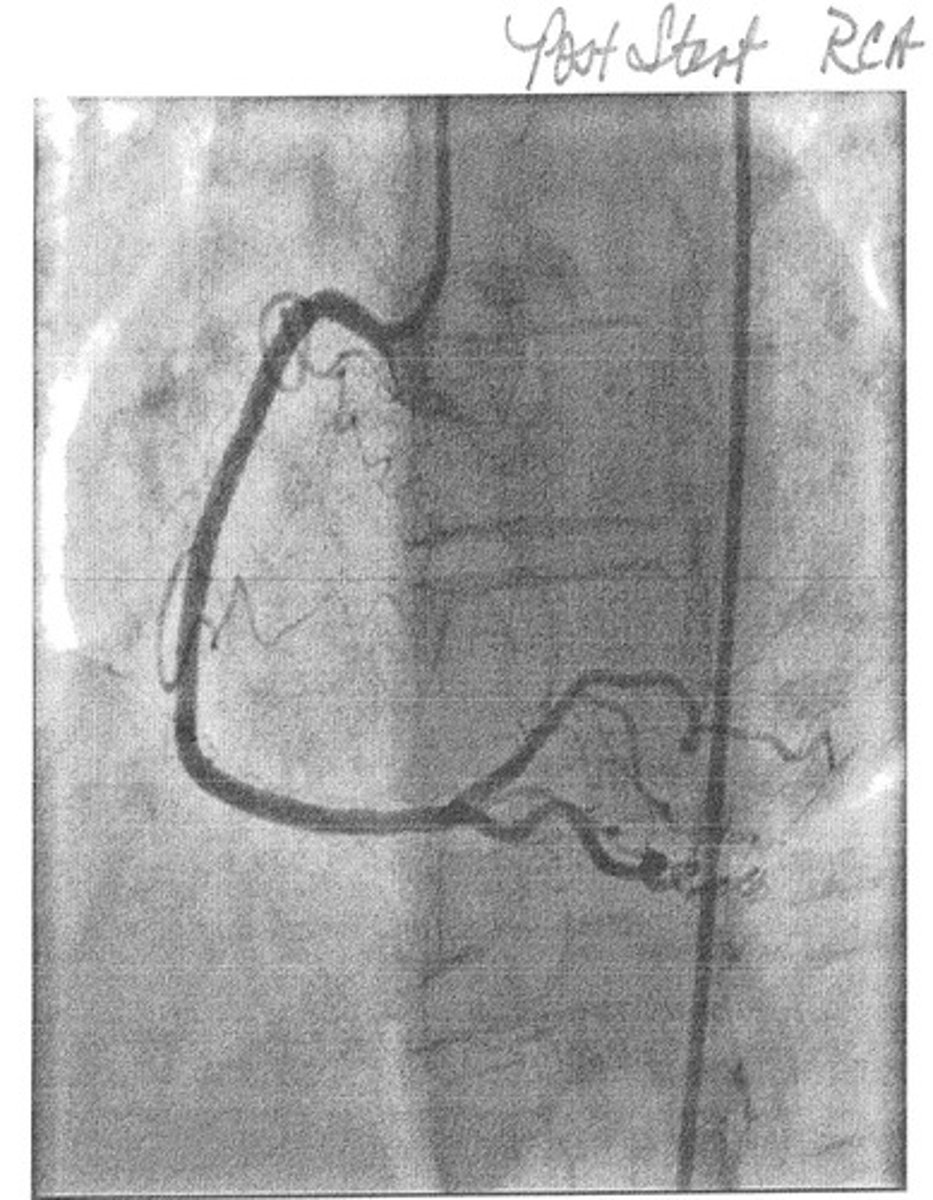

Right Coronary Artery (RCA)

Supplies blood to the right atrium, right ventricle, and inferior and posterior walls of the left ventricle.